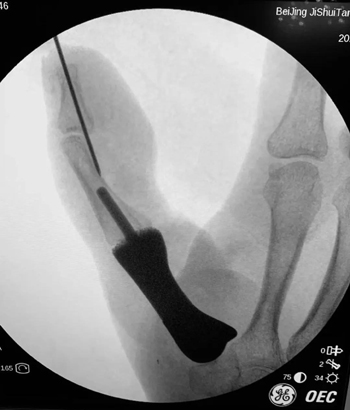

陈山林主任团队术前详细规划,反复推演手术流程,3月5日,在陈山林主任、薛云皓副主任医师、杨辰主治医师、刘畅住院总医师的共同协作下,顺利完成了假体置入,腕掌关节韧带重建,游离穿支嵌合皮瓣移植等复杂精细手术。手术过程非常顺利,术中影像显示,假体位置满意,腕掌关节稳定且具备一定的活动度。再造拇指外观满意,长度合适,各皮瓣存活良好。足部供区外观良好。“手术能够顺利完成,要特别感谢医务部、疾控/院感处、手术室、麻醉科等各个部门对手外科开展新技术给予的全力支持和政策保障。”陈山林主任说。

为了保住左手功能,患者慕名来到积水潭医院手外科就诊。陈山林主任检查后发现,他的左手第一系列缺失,若采用传统踇甲瓣结合髂骨移植等办法进行拇指再造,不仅重建的掌骨有被吸收掉的风险,而且患者无法获得有功能的腕掌关节,然而稳定且可活动的腕掌关节恰恰在发挥拇指功能中是最为重要的一环。考虑患者左手仍保留完整的大多角骨,陈山林团队决定为患者定制化制作金属3D打印的第一掌骨,满足患者第一腕掌关节的解剖学重建,为患者的拇指再造提供了一个良好的骨性基础。经文献检索,该技术属于世界首创!